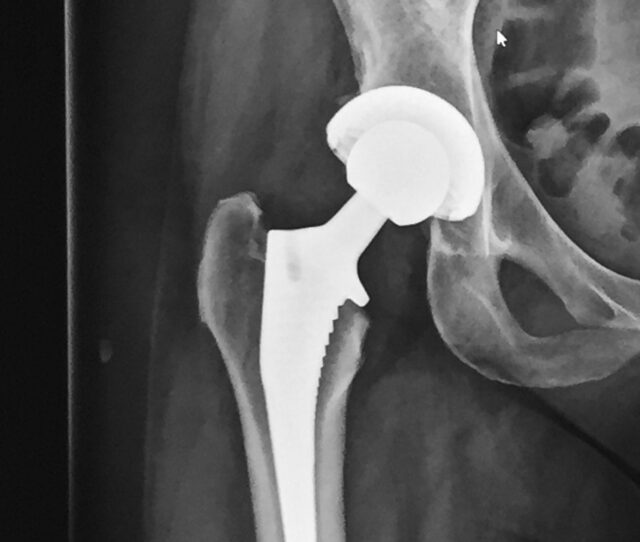

Het type prothese (Corail van de firma Depuy) die dr. Henkus daarvoor gebruikt, gaat inmiddels al zeker 25 jaar mee en hopelijk nog langer. Dat moet de toekomst nog uitwijzen. “Doordat deze kunstheupen het zo goed blijken te doen, kunnen we wat gemakkelijker ook mensen jonger dan 60, zoals Wendy en Caroline een nieuwe heupprothese te geven”, legt Hans-Erik Henkus uit.